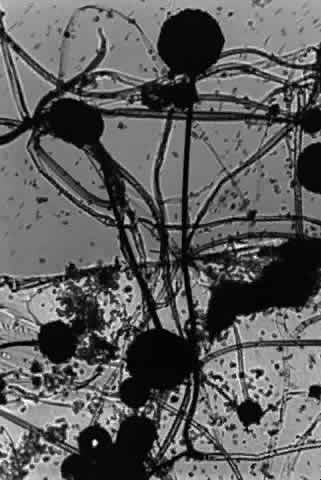

ASPERGILLUS SPECIES.

Growth matures within 2 to 6 days. Colonies are white, blue green, green, yellow, brown, or black. Reverse is white, gold, or brown. Colonies are flat, wrinkled or furrowed, with a velvety or cottony texture. Microscopic findings include large, septated hyphae. Simple, unbranched conidiophores arise from a foot cell and are enlarged at the tip (vesicle). Each conidiophore is covered partially or completely with one or two rows of flask-shaped phialides with chains of conidia (Fig. 1).

Fig. 1. Growth of Aspergillus fumigatus on malt agar showing chains of phialoconidia that form the head (X 25).